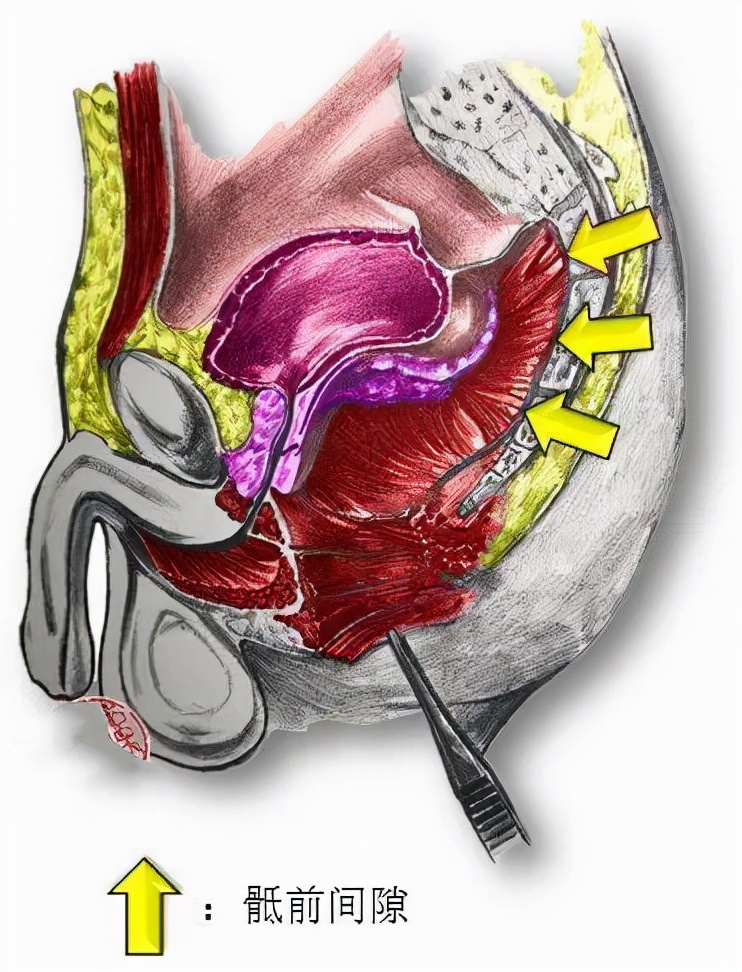

且骶前间隙是一个潜在的间隙, 周围比邻结构复杂 ,外科处理非常困难。

男性骶前间隙

术中容易损伤

盆底的肌肉和直肠

大大增加手术难度